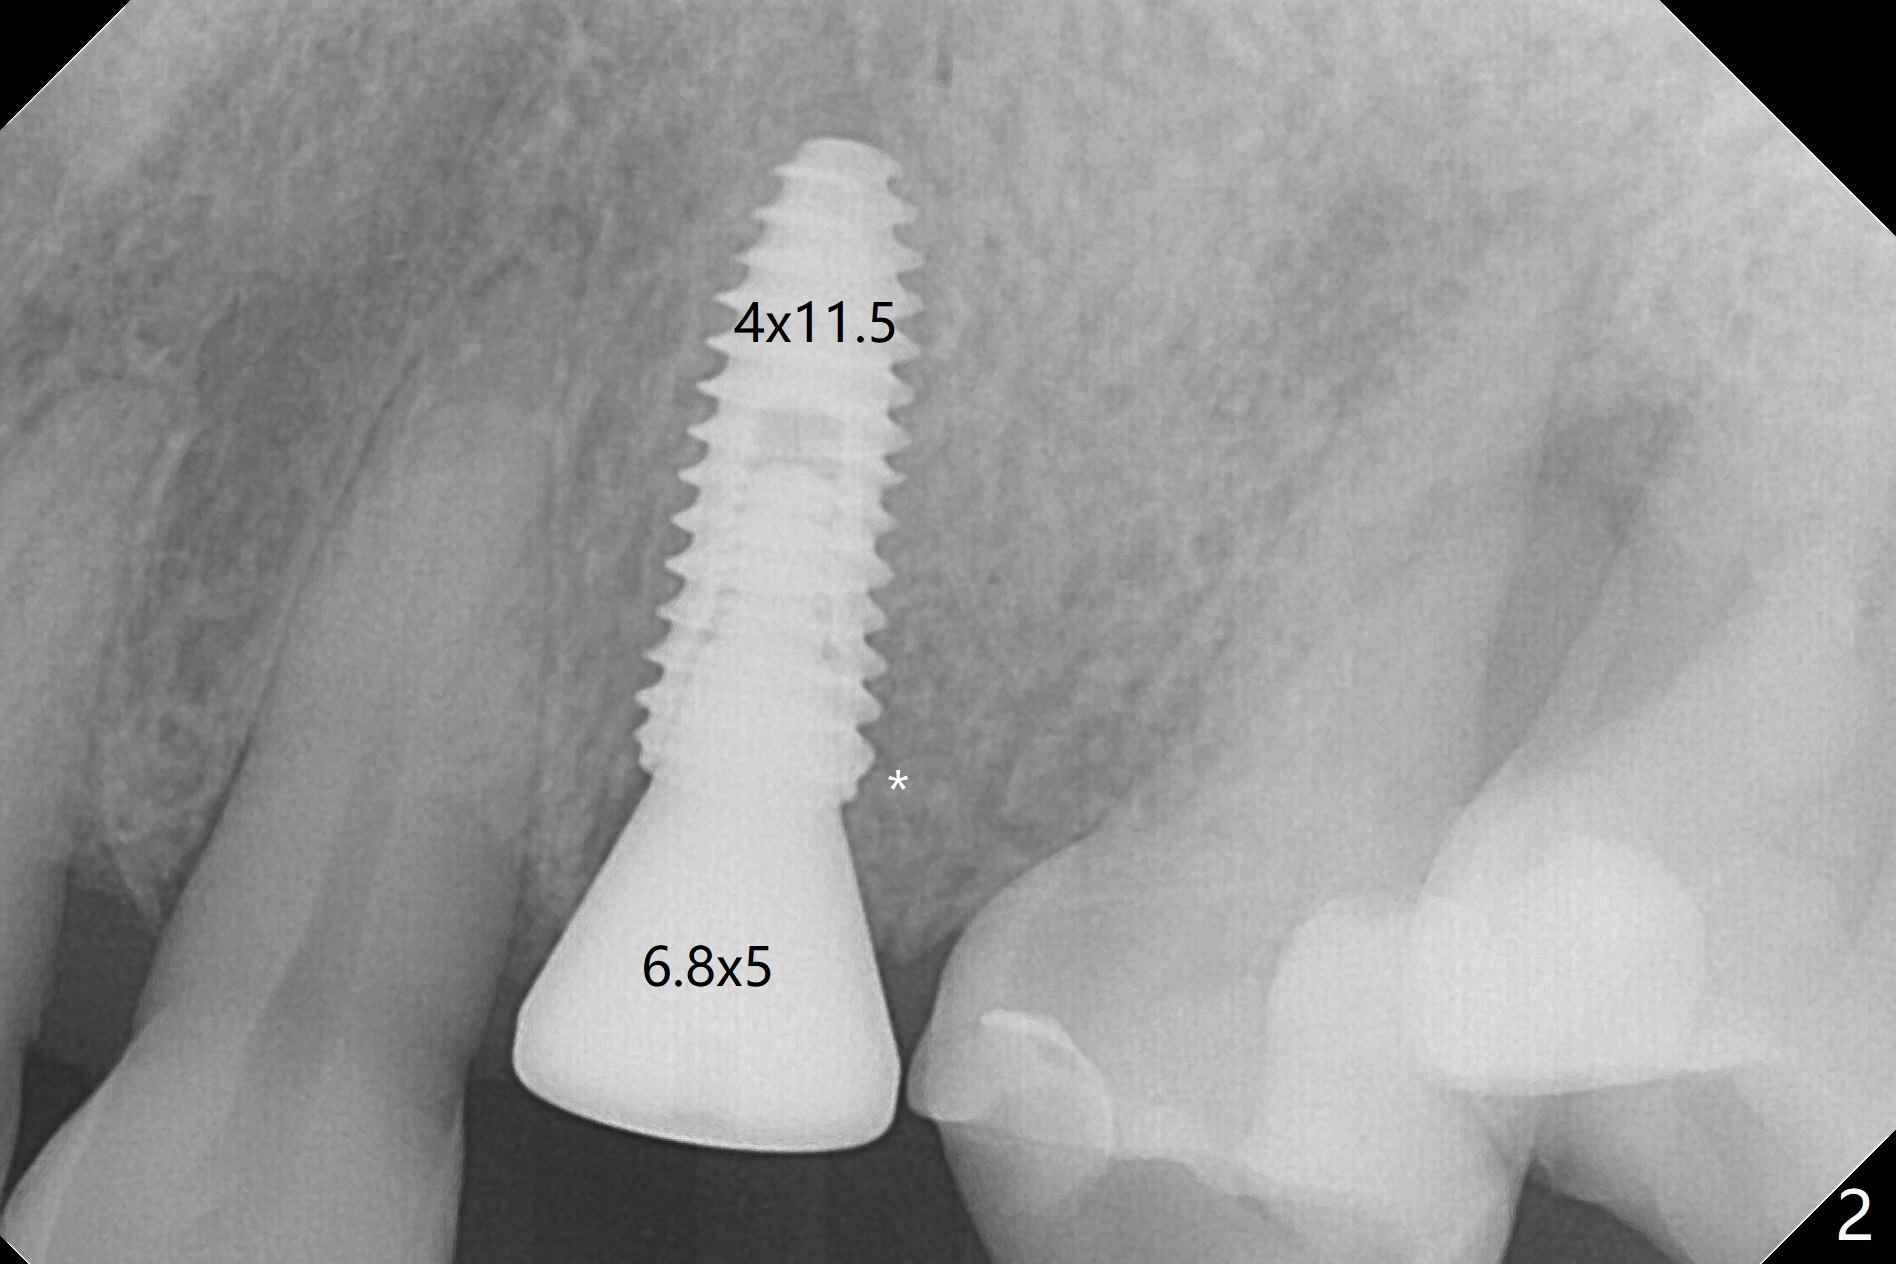

PA is taken after a 2.2 mm drill reaches the depth at #12, since osteotomy is initiated in the mesial slope of the socket (Fig.1 red dashed line) and the neighboring root (*) slightly curves distal. A 8.6x5 mm healing abutment is used to close the socket with the large mesiodistal space after bone graft (Fig.2 *). In contrast, the socket at #20 is large; a 4.5x4.5(3) mm cementation abutment is placed for an immediate provisional to keep autogenous bone (harvested from the site of #18) in place (Fig.3). Six months postop, the patient does not want implant FPD. She wants an additional implant at #19. Since the space between the implants #18 and 20 is 9.41 mm, a narrow implant is indicated (3 or 3.5 mm, Fig.4), in spite of the sufficient buccolingual width (Fig.5). The position and trajectory of the 1.2 mm initial drill and 3x10(2) mm 1-piece implant are acceptable with free hand (Fig.6,7). After 3-4 more turns, panoramic X-ray (Fig.8) and CT (Fig.9) are taken for 28-30 guide. It appears that the 1-piece implant is placed acceptable buccolingual (Fig.9 B). The implants at #12,18,20 (4.5 months postop with guide) are shown in Fig.10-12. It appears that guided surgery is superior in buccolingual position and trajectory to free hand. There is crestal remodeling without implant thread exposure 11 months postop (Fig.13).